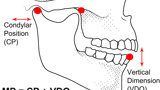

Fig. 4: Mandibular position defined as condylar position and vertical dimension of occlusion.

Fig. 5: Occlusion represented as mandibular position and intercuspation.